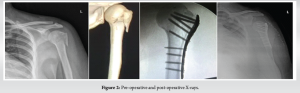

Post-operatively, the arm was immobilized using a shoulder immobilizer for all 20 patients. The time for commencement of shoulder physiotherapy was based on the stability of fixation, quality of bone, and compliance of the patient. Passive range of movement exercises, such as pendulums, passive forward elevation, and external rotation, were generally started on the 1st post-operative day, provided that a stable reduction was achieved. Active range of movements of the elbow, wrist, and hand was also started on the 1st post-operative day. Early passive assisted exercises, active exercises were started at approximately 6 weeks post-operatively and strengthening or resistance exercises started at 10–12 weeks post-operatively. Post-operative X-rays were taken after 24 h of surgery to check the fracture alignment, reduction, and fixation [Fig. 2]. Routine follow-up radiographs were taken after 4 weeks, 3 months, 6 months and 12 months post-operatively to evaluate the features of union, such as disappearance of fracture line, inner column continuity, trabecular continuity, calcar screw status, maintenance of neck shaft angle, and plate related complications, such as screw penetration, screw cut out, avascular necrosis, and implant loosening [Fig. 3,4]. Common post-operative complications are restricted movements associated with pain, operative site infection, fixation failure, avascular necrosis of the head, and sometimes late rupture of the cuff muscles [7].